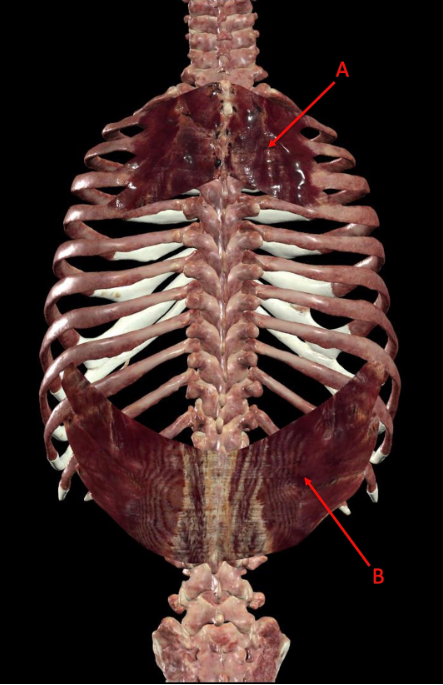

A. serratus posterior superior

B. serratus posterior inferior